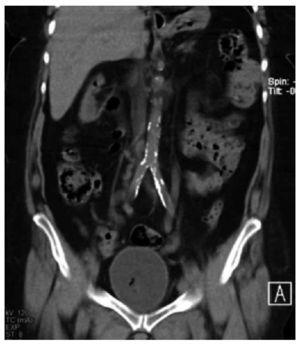

El caso que presentamos es una paciente con infección de vías urinarias complicada en pielonefritis enfisematosa bilateral, secundaria a uropatía obstructiva por la vena ovárica bilateral, por lo anterior tiene la particularidad de estar en el 11% de la presentación general, ya que dentro de los estudios de imagen no se evidenció la presencia de otro proceso obstructivo que condicionara la ureteropielocaliectasia y por consiguiente, el proceso enfisematoso. El cuadro clínico fue muy inespecífico, y la paciente fue ingresada por complicación de una pielonefritis enfisematosa. En la Figura 1, se observa un proceso enfisematoso en el uréter en el tercio proximal derecho. En la Figura 2, se observa ectasia bilateral con gas en parénquima renal en el polo superior derecho y en las cavidades del riñón izquierdo, así como el uréter del mismo lado, también se alcanza a observar la presencia de una escotadura en el uréter superior izquierdo y algo del derecho, justo por debajo de la unión ureteropiélica, que es el lugar donde se cruza con la vena ovárica.

Figura 2. Ectasia bilateral con gas en parénquima renal polo superior derecho y en cavidades de riñón izquierdo, así como del uréter del mismo lado, presencia de escotadura en uréter superior izquierdo y del derecho, justo por debajo de la unión ureteropiélica, donde se cruza con la vena ovárica.

En la Figura 3 se observa como la vena ovárica izquierda ingresa a la vena renal ipsilateral, produciendo ectasia ureteral desde el cruce de las ilíacas, se demuestra que es el sitio donde se cruza el uréter y la vena ovárica, allí se manifiesta la escotadura antes mencionadas, también demostrándose en esta figura la ectasia derecha con gas parenquimatoso hacia el polo superior. En la Figura 4 resalta del lado derecho, justo donde se cruza la vena ovárica con el uréter es donde se produce la ectasia a nivel de la bifurcación de la aorta en ilíacas primitivas, y del lado izquierdo en el cruce ureteral con los vasos ilíacos nuevamente se cruza con la vena ovárica produciendo ectasia.

Figura 3. Vena ovárica ingresando por la vena renal izquierda ipsi-lateral, produciendo ectasia ureteral desde el cruce de los ilíacos. Se demuestra sitio donde se cruza uréter y vena ovárica, allí se manifiesta la escotadura antes mencionada. También se observa ectasia derecha con gas parenquimatoso hacia polo superior.